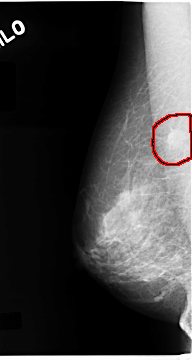

C_0115_1.LEFT_MLO

LEFT_MLO LINES 4720 PIXELS_PER_LINE 2408 BITS_PER_PIXEL 12 RESOLUTION 50 NON_OVERLAY

FILE: C_0115_1.RIGHT_MLO.OVERLAY

TOTAL_ABNORMALITIES 1

ABNORMALITY 1

LESION_TYPE MASS SHAPE ROUND MARGINS SPICULATED

ASSESSMENT 5

SUBTLETY 5

PATHOLOGY MALIGNANT

TOTAL_OUTLINES 1

BOUNDARY